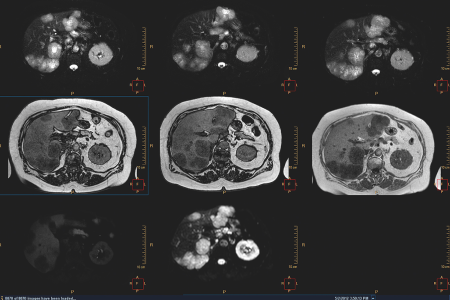

Fortschrittliche Visualisierungs-Tools für die Onkologie zur Beurteilung des Krankheitsstadiums und des Ansprechens auf die Behandlung

Multi Modality Tumor Tracking

Lösungen für Molekular- und Hybridbildgebung mit niedriger Dosis und mit klinischen Anwendungen zur Therapieüberwachung

Nuklearmedizin image

Umfassende Ultraschalllösungen zur Beurteilung und Überwachung von Brust, Leber und Prostata

Ultraschalllösungen für die Onkologie